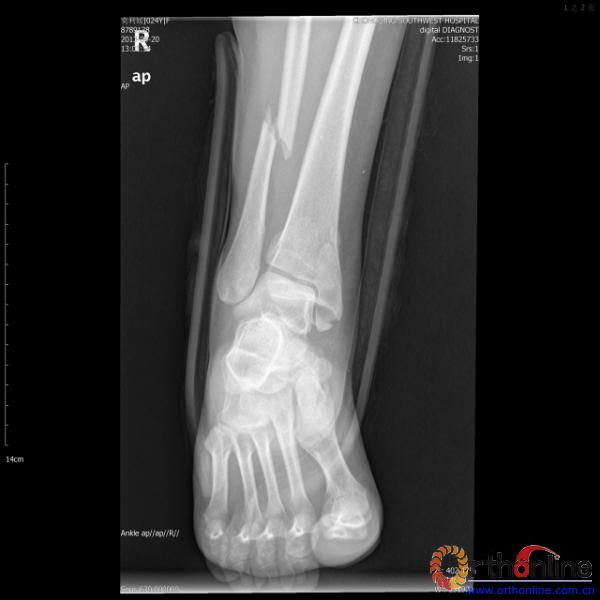

2013年4月20日 8:02分四川雅安芦山县发生7.0级地震后,重庆市有震感,24岁的莫老师在赶往上班的途中突遇此事,导致右踝关节畸形,不能站立和行走。

伤员和家属迅速赶到西南医院,10点关节外科段小军副教授查看伤员后急诊收入院,拍摄X片和急诊行三维CT重建检查,提示踝关节创伤严重,出现三踝骨折伴胫距关节脱位,需要急诊手术治疗。随后段教授与正在四川成都参加“汶川地震5周年灾害医学救治研讨会”的杨柳主任联系,进一步完善救治方案。地震当晚,段教授为该伤员进行急诊手术,手术顺利对复杂骨折进行了解剖复位,有效的钢板螺钉固定。术后伤员的疼痛明显缓解,复查X片,踝关节结构恢复满意。

患者术前X片(一)